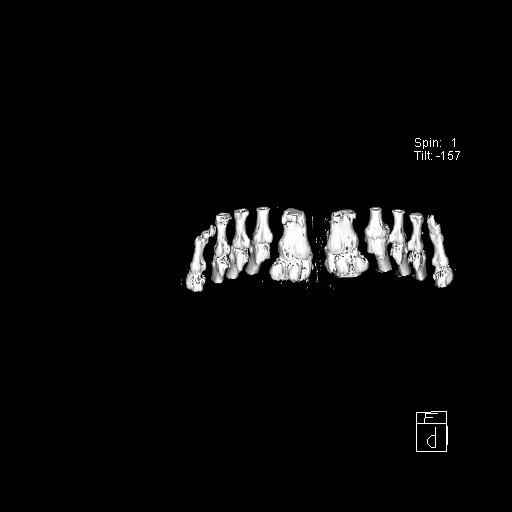

标题: CT13415:M72Y,跖趾关节病变,请会诊 [打印本页]

标题: CT13415:M72Y,跖趾关节病变,请会诊

男72岁左侧跖趾关节肿痛15年,查压痛。